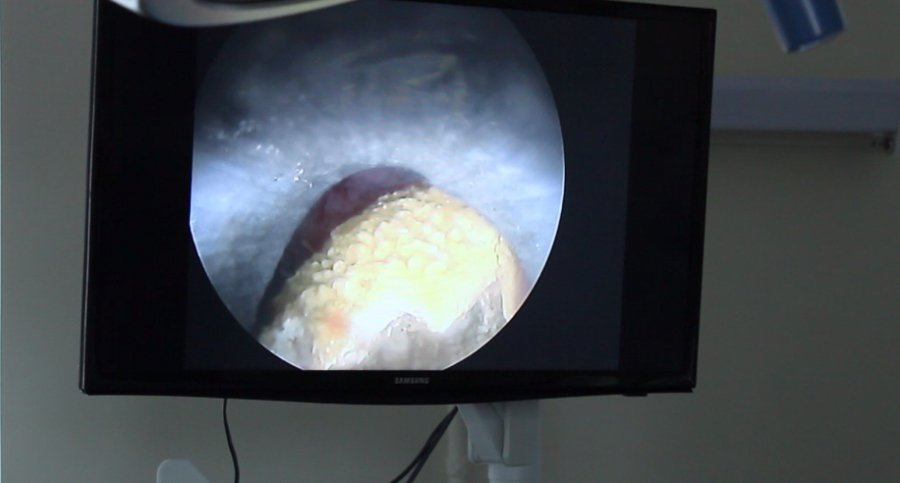

Зазначили, що «найцікавішим» випадком було видалення великого кораловидного конкременту (каменя, – ред.). Він займав всю ниркову миску і нижню чашку.

Команда урологів успішно провела черезшкірне дроблення та видалила камінь повністю.